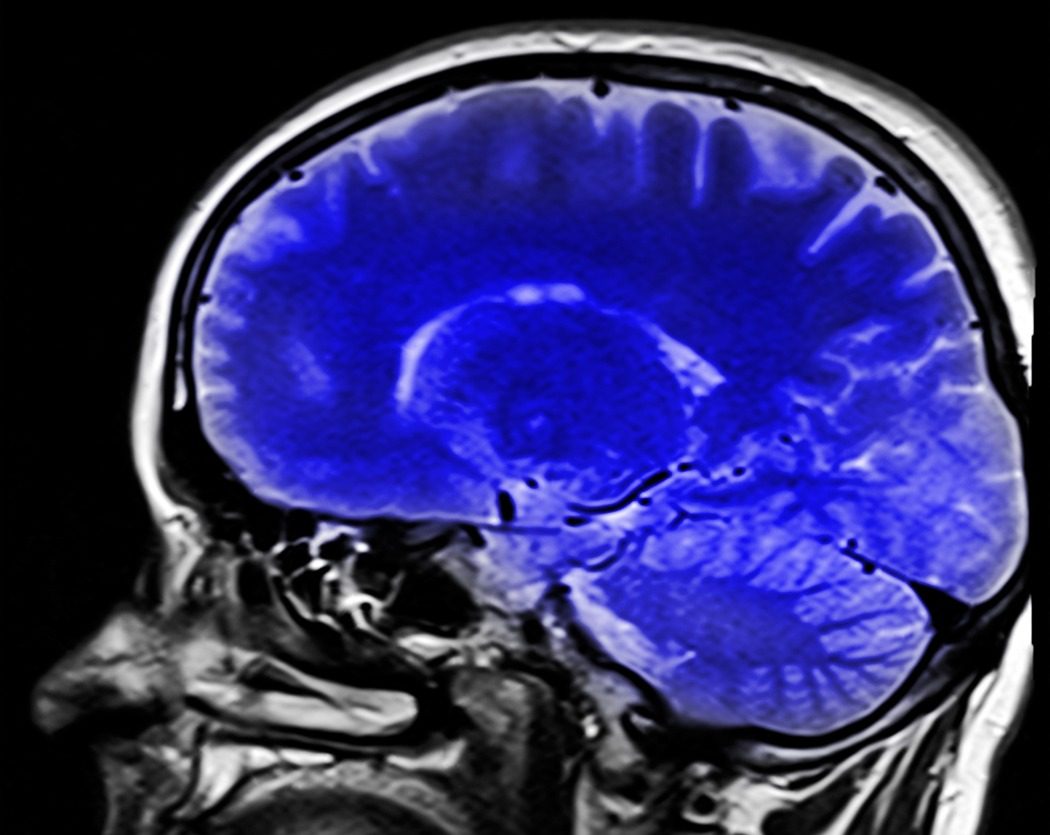

Эта аллегории удачна только тем, что в ней присутствуют голова и кровь. Если в результате баталии последней было море, то в случае патологии как раз ее и не хватает. Инсультом называют острое нарушение кровоснабжения тканей головного мозга. Причиной внезапного дефицита может быть:

Лишившись кислорода, клетки органа, руководящего телом, начинают погибать. Современной медицине под силу вырвать из лап смерти большинство жертв Кондрашки, но после знакомства с этим персонажем несчастных ждет длительная реабилитация, и нередко инвалидность.